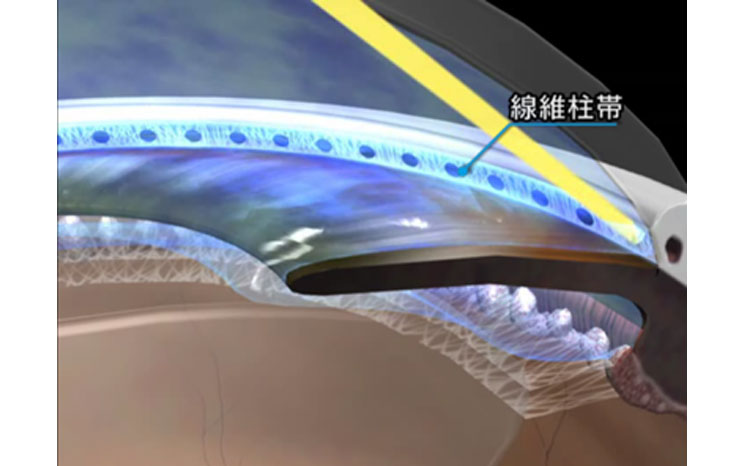

レーザー線維柱帯形成術

線維柱帯切除術

- 流出路再建術